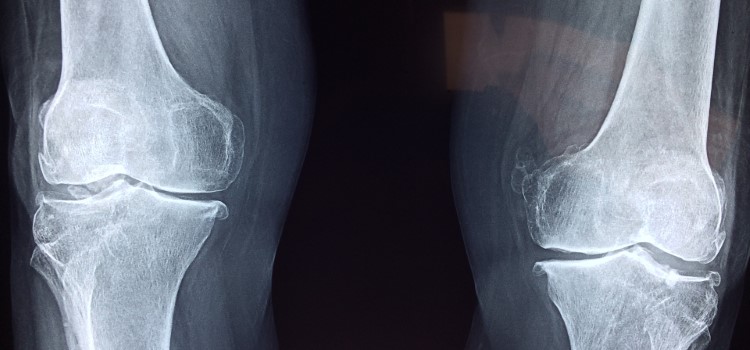

Un grupo internacional de investigación liderado por el científico español Javier Llorca, director científico del instituto IMDEA Materiales, ha logrado poner a punto la técnica para la impresión en 3D de andamios óseos de magnesio. Las fracturas óseas pequeñas se reparan con clavos o placas que unen y fijan los dos extremos del hueso roto. Pero esta estrategia no sirve cuando esas lesiones son más importantes, por ejemplo si ha habido que eliminar un fragmento de hueso por un tumor o la rotura ha sido muy grave y ha desparecido una porción del tejido óseo. En estas ocasiones, es necesario implantar un andamio que reemplace al hueso mientras se produce la regeneración ósea. Este andamio debe ser poroso -para permitir el crecimiento del tejido óseo- y tener las dimensiones y forma del fragmento desaparecido.  En el caso de los huesos que no deben soportar mucha tensión estas estructuras pueden fabricarse con polímeros mediante impresión en 3D. Sin embargo, los polímeros no se pueden utilizar en los huesos que soportan grandes esfuerzos mecánicos (como los huesos largos o el maxilar) por su pobre resistencia mecánica. En esas ocasiones es necesario usar andamios metálicos.

Una de las características clave en esos andamios es controlar la porosidad -de modo que pueda producirse la vascularización y el crecimiento celular- al mismo tiempo que se aseguran las necesarias propiedades mecánicas. Pero una estructura de esas características y que se adapte perfectamente a la región lesionada del paciente es muy difícil de fabricar. Hasta ahora, las únicas posibilidades para lograr estos objetivos era la fabricación por impresión 3D de aleaciones metálicas biocompatibles (acero inoxidable, titanio) que no son biodegradables. En consecuencia, el andamio metálico permanece de por vida en el paciente y puede dar lugar a complicaciones a largo plazo debido a la presencia de un material extraño. Una aproximación más prometedora para resolver este problema es utilizar un metal biodegradable que el organismo metabolice progresivamente una vez que el tejido óseo se ha regenerado.

Existe un metal que cumple esos requisitos, el magnesio. Pero la impresión 3D de andamios porosos de magnesio es problemática porque sus temperaturas de fusión y evaporación son muy próximas. La fusión del polvo de magnesio mediante un láser en la impresora 3D produce la evaporación de una gran parte del material e impedía la fabricación de estructuras con dimensiones precisas. El primer gran logro del equipo liderado por Javier Llorca ha sido superar esas dificultades al conseguir imprimir en 3D andamios con una porosidad controlada y optimizada para favorecer la regeneración del hueso. Pero el trabajo no se ha quedado solo ahí, también han desarrollado tratamientos térmicos y superficiales para que la velocidad de degradación del andamio se ajuste al tiempo necesario para la regeneración del tejido óseo. En su investigación, además, han demostrado que tanto las aleaciones de magnesio como los materiales resultantes de la degradación del andamio no son citotóxicos y permiten la proliferación celular.